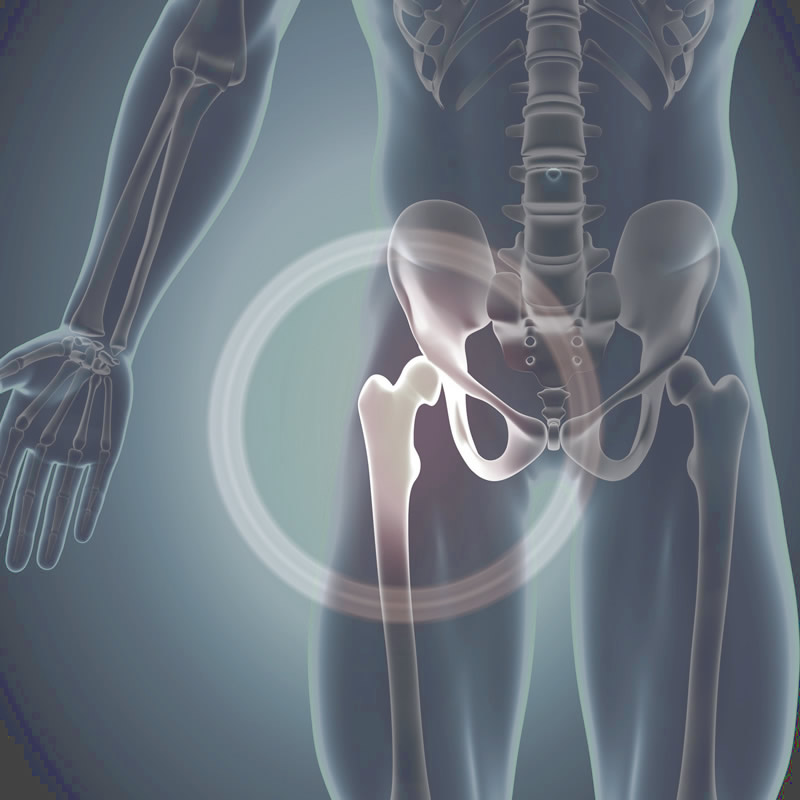

主治項目